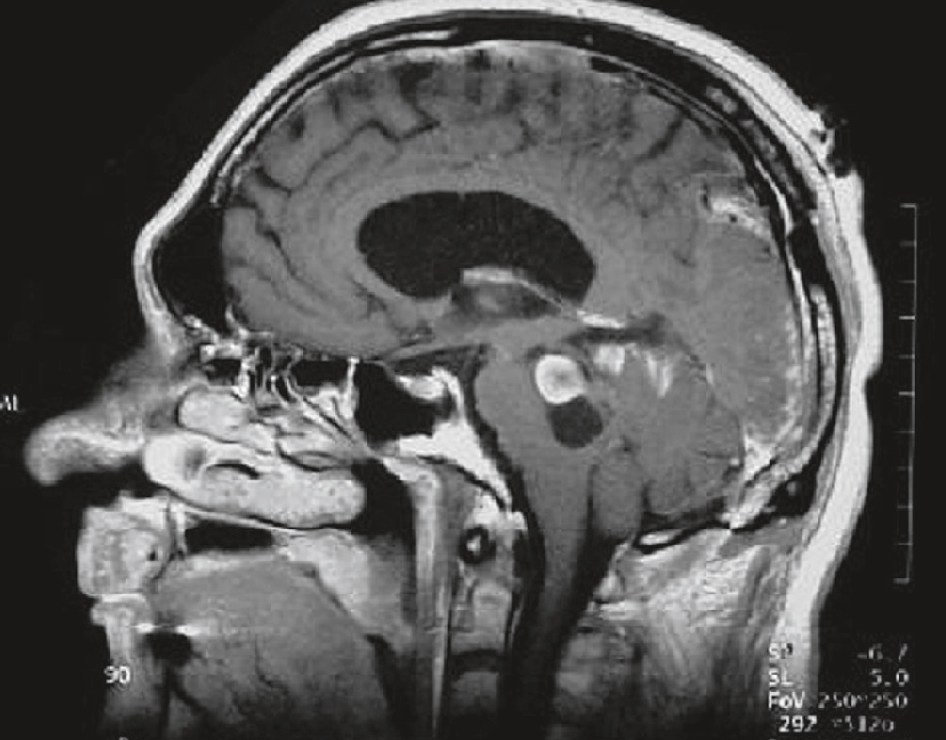

IRM cérébrale d’un patient de 22 ans présentant un tableau d’HTIC. Séquence T1 avec injection de gadolinium, coupe sagittale : lésion du tronc cérébral constituée d’une partie nodulaire prenant le contraste et d’une portion kystique (hyposignal). Hydrocéphalie (dilatation ventriculaire).

Image d’IRM cérébrale en coupe sagittale chez un patient de 22 ans présentant un tableau d’hypertension intracrânienne (HTIC). On observe une volumineuse lésion arrondie, hyperintense et bien circonscrite, située dans la région du tronc cérébral, probablement au niveau du mésencéphale ou du pont, avec un effet de masse visible sur les structures adjacentes. Cette masse entraîne un écrasement des espaces sous-arachnoïdiens et une déformation des ventricules, traduisant une obstruction possible à l’écoulement du liquide cérébrospinal, compatible avec une HTIC. Le parenchyme cérébral environnant semble refoulé, ce qui souligne la pression exercée par la lésion intracrânienne.